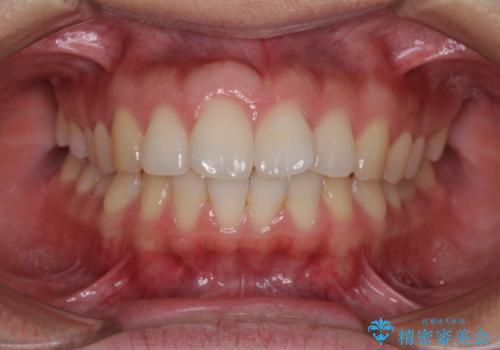

- 前歯の出っ歯と口元の閉じにくさを気にして来院された患者様です。

口元を積極的に引っ込めるために、上下左右の小臼歯4本を抜歯することとしました。

4本の歯を抜歯したことで、飛び出していた口元が引っ込み、横顔が大きく改善されました。

咬み合わせが悪化することのないようにスペースを閉じていくことができ、比較的スムーズに治療を進めることができました。